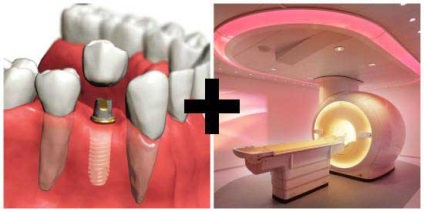

Tehetek egy MRI implantátumok - felelős szakember

Amikor a beteg implantátumok kerültek beépítésre, a további szükséges betartani az összes ajánlásait az kezelőorvos. Ebben az esetben van szükség, hogy aktívan vigyázni a design, hogy meghosszabbítja az élettartamát. De van számos eljárást, amelyre szükség van, hogy vegye figyelembe a jelenléte ezen fogászati termékek. Tehetek egy MRI implantátum? Mielőtt a magatartás, szükséges, hogy figyelmeztesse a jelenléte fogsor.

Tehetek egy MRI implantátum fogakat? Ez a kérdés fontos ma, mint a legutóbbi időkig, egy felmérés történik radiológia. És ez csak elvégzi a diagnózis a csontszövet.

Ami az MRI. ez egy innovatív módon, hogy feltérképezzük a használatát, amelyek megtalálhatók teljesen bármilyen patológiás folyamat korai szakaszában a fejlődését. MRI segítségével fogorvosok, hogy vizsgálja meg a csontszerkezet a fogak, és a porcok és a környező lágyrészek.

MRI és a fogászati implantátumok - Vannak olyan ellenjavallatok? Ahhoz, hogy erre a kérdésre válaszolni, meg kell értenünk, először, mik a jelek erre az eljárásra. Köszönhetően a mágneses rezonancia képalkotó lehet érteni, ha a vizsgált személy betegnek szüksége sebészi kezelés, vagy a gyógyszeres terápia tehetünk.

Anyagok fogászati struktúrák és MRI

Ez milyen anyag részt a fogászati korona, ez attól függ, hogy tud-e tenni implantátummal MRI. Néhány évvel ezelőtt, ezek a konstrukciók a fémrészeket a rézötvözet arannyal vagy acélból. MRI berendezés nincs érzékelhető hatása, de itt van egy kép során kapott a tanulmány, fuzzy. Ma, fogászati betegek set-fém implantátumok, amelyek lehetővé teszik a folyosón MRI, és nem befolyásolja a kép minőségét.

Legközelebb - ez is része a korona. Ezek közé tartozik a csavarokat és csapok. Mert azok gyártási használatával paramágneses, ferromágneses és diamágnesesek. Ezek befolyásolják a mágneses mező, amely létrehoz egy MRI gép. Meg kell figyelembe venni a forma, ami jellemző a fogászati szerkezetek biztonságos. Úgy történik, hogy bizonyos ferromágneses anyagok hatása alatt a mágneses mező felmelegszenek vagy mozog.

Ha az eredmény hiánya MRI?

Az egyetlen kellemetlen dolog, ami akkor történhet, ha ezt a felmérést, ez torzítja az eredményeket. Emiatt minden beteg, aki azt tervezi, hogy végezzen MRI értesítenie kell profi. Bár van egy mellékhatása ezeknek a betegeknek is lehetővé tette, hogy nem egy MRI. Megkezdése előtt orvosa változtatni kell az összes szükséges beállítást. Aztán a kép tiszta és hibamentes.

MRI és fém koronák

MRI a fogak és az állkapocs betegek felírt nagyon ritkán. Ennek az az oka, hogy a száj - ez egy nagyon távoli helyen. Alkalmazni tomográfia fájdalmas érzés rágás közben, görcs az állkapocs izmok és korlátozott állkapocs mobilitást. A betegek, akik fém korona volt telepítve, gyakran gondolt fogászati korona az eljárás során, hogy sérült.

Végezze MRIs megtehetnek ebben az esetben, mert a legtöbb fogászati fogászati szerkezetek alapján készült polimer ötvözetek, és nem reagál a mágneses mező a hullám. Ha a korona közé ferromágneses anyagok, a magatartása MRI csak akkor lehetséges engedélyével az orvos. Egyes klinikák modern berendezés, amely nincs hatással az elmozdulás és a fűtés ferromagneticheskih ötvözetek.

Más esetekben, a betegek tisztában kell lenniük azzal, hogy a fém koronák és kerámia-fém szerkezet az ötvözet vált oka elmosódás. Ezért, hogy a döntést csak az orvos képes lesz folytatni ezt a felmérést. Ha a klinika nem rendelkezik a megfelelő felszereléssel, a betegek fogászati implantátumok nem fogja elvégezni MRI. Az egészségügyi központok, ahol van egy innovatív eszközök, szakemberek képesek megváltoztatni a beállításokat, és kap egy minőségi kép a teszt után. Az orvos közli az eredményeket a teljes munkaidőben, meg kell, hogy adjanak neki egy röntgen. Vannak esetek, amikor a beteg kérte, hogy távolítsa koronák, ha lehetséges, és MRI helyébe komputertomográfia.

Mágneses rezonancia képalkotás - egy innovatív módszer a diagnózis az emberi test, vannak olyan helyzetek, amikor nem lehet elvégezni. Ez a megkötés vonatkozik azoknak a betegeknek, akik a fogászati implantátumok. Ebben az esetben a tapasztalat a tervezés önmagában nem szükséges, mert egyáltalán nem sérült a mágneses mező, de a kapott eredmények homályos és elmosódott. E helyzet enyhítése érdekében, akkor egyszerűen kell, hogy előre értesítse kezelőorvosát az implantátumok állnak rendelkezésre, és azt követően, hogy döntést hoz a megvalósíthatóságát a diagnózist.